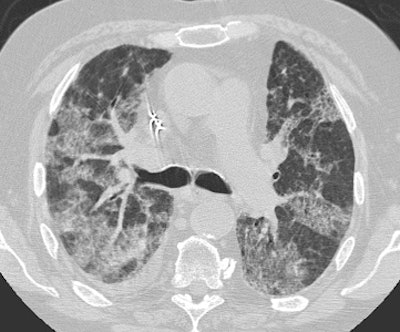

Diffuse Alveolar Damage: The patient below was admitted to the intensive care unit with increasing dyspnea. HRCT imaging revealed patchy areas of ground glass opacity and consolidation within the lungs bilaterally. There were prominent underlying reticulations within the areas of airspace disease. An open lung biopsy was performed and demonstrated diffuse alveolar damage. The etiology was not clinically apparent. |

![]() ![]() |